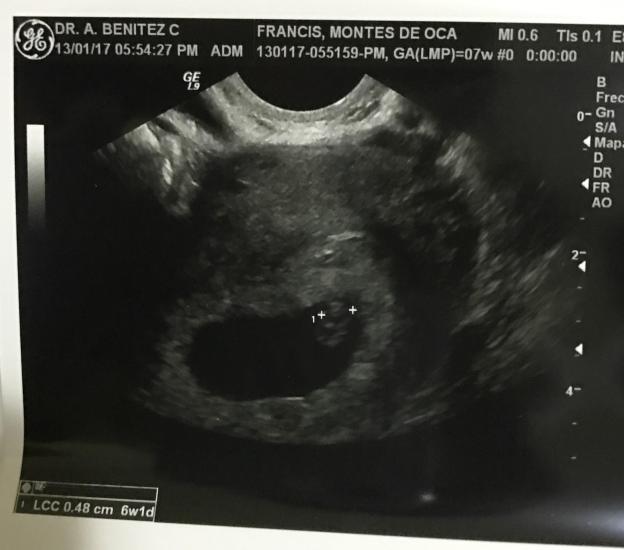

Esa misma semana hice mi cita con mi ginecólogo y tuvimos nuestro primer eco (Viernes 13 de enero) . En esa consulta escuchamos el corazón del bebé y bueno, como verán en la foto, no se veía mucho pero para mi era una oruguita que pronto se iba a convertir en un bello y hermoso bebé. Ese día llamé a mi mamá que estaba en Venezuela para contarle la noticia pero le dije que quería esperar que avanzara unas semanas más para contarle a todo el mundo.